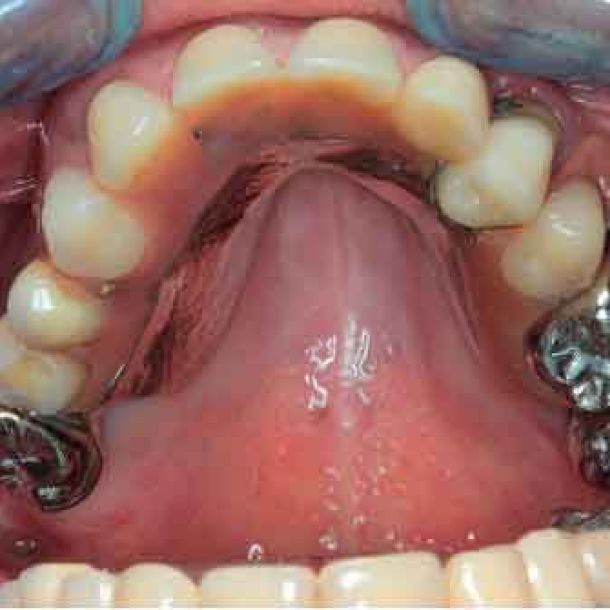

Step 4 - DATA EXPORT TO THE DENTAL LABORATORY

During the initial appointment, comprehensive data collection is essential. From pictures to segmented DICOM files and jaw motion data, all information is integrated into the TWIM software, streamlining communication with the dental laboratory.

- Pictures

- IOS scans (incorrect but still useful for the dental technician)

- DICOM files, segmented into STL files

- Jaw motion data : individual patient data to parameter the virtual articulator

- Facescan (optional)

The dataset is sent to the lab to design the provisionals.